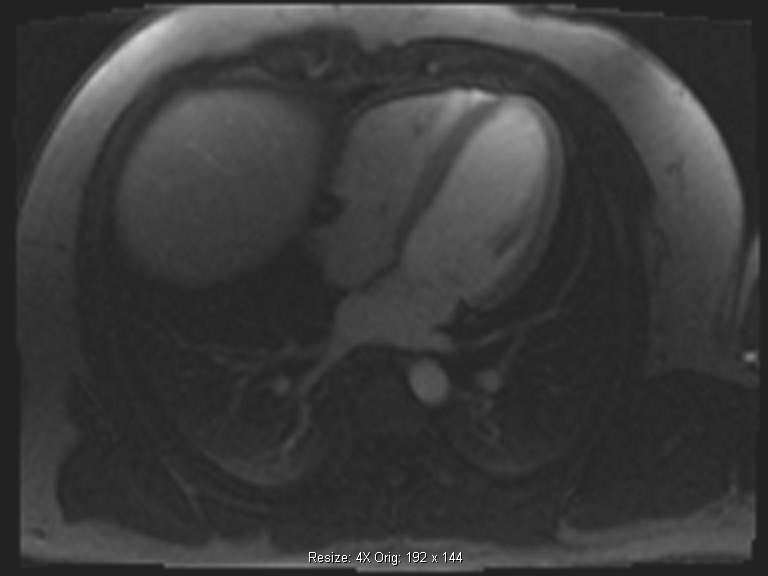

Τα βασικότερα πλεονεκτήματα της δυναμικής μαγνητικής τομογραφίας καρδιάς με αδενοσίνη (adenodine stress perfusion MRI) είναι η υψηλότερη ευαισθησία και ειδικότητα σε σχέση με τις υπόλοιπες διαγνωστικές μεθόδους δυναμικής απεικόνισης (σπινθηρογράφημα μυοκαρδίου, stress echo), η καταγραφή ακόμα και μικρών υπενδοκάρδιων ισχαιμικών περιοχών και μυοκαρδιακών ουλών, η καλύτερη διακριτική ικανότητα σε σχέση με το σπινθηρογράφημα του μυοκαρδίου και η ασφάλεια λόγω της απουσίας έκθεσης σε ιονίζουσα ακτινοβολία (εικόνες 1,2).

Εικόνα 1. Δυναμική μαγνητική τομογραφία καρδιάς με αδενοσίνη: